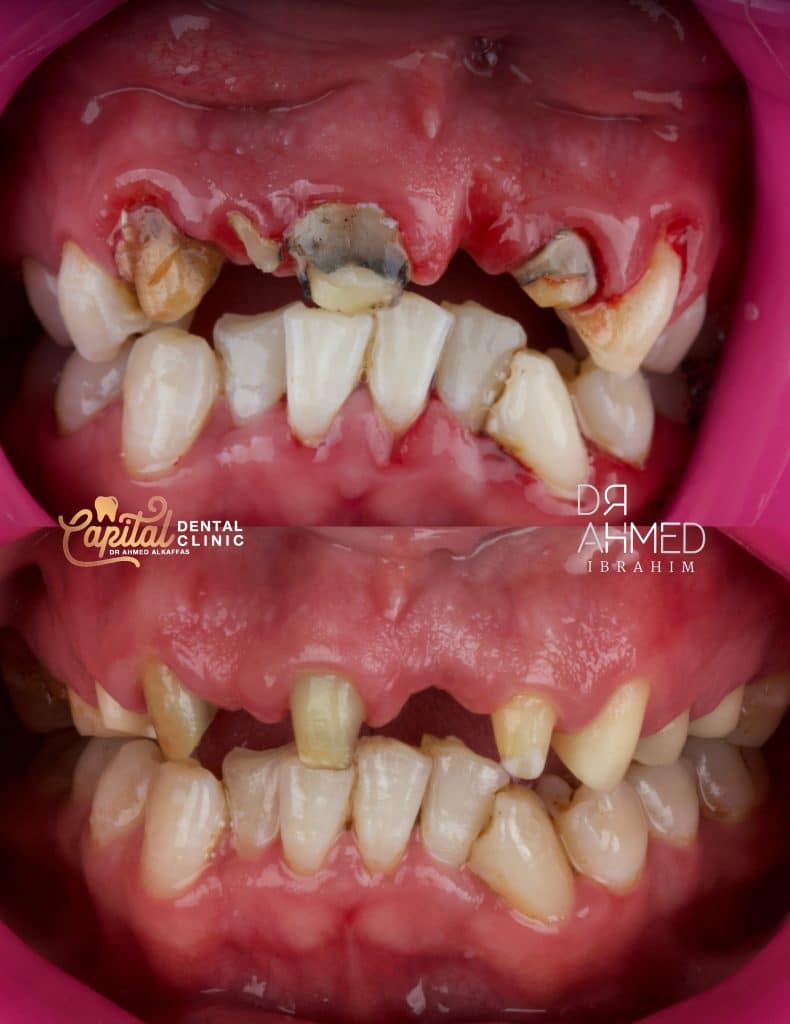

After scaling and removal of old crowns and bridge

Temporary after laser treatment that will last for 2 weeks

Post and core build up then reduction

Old preps vs new preps